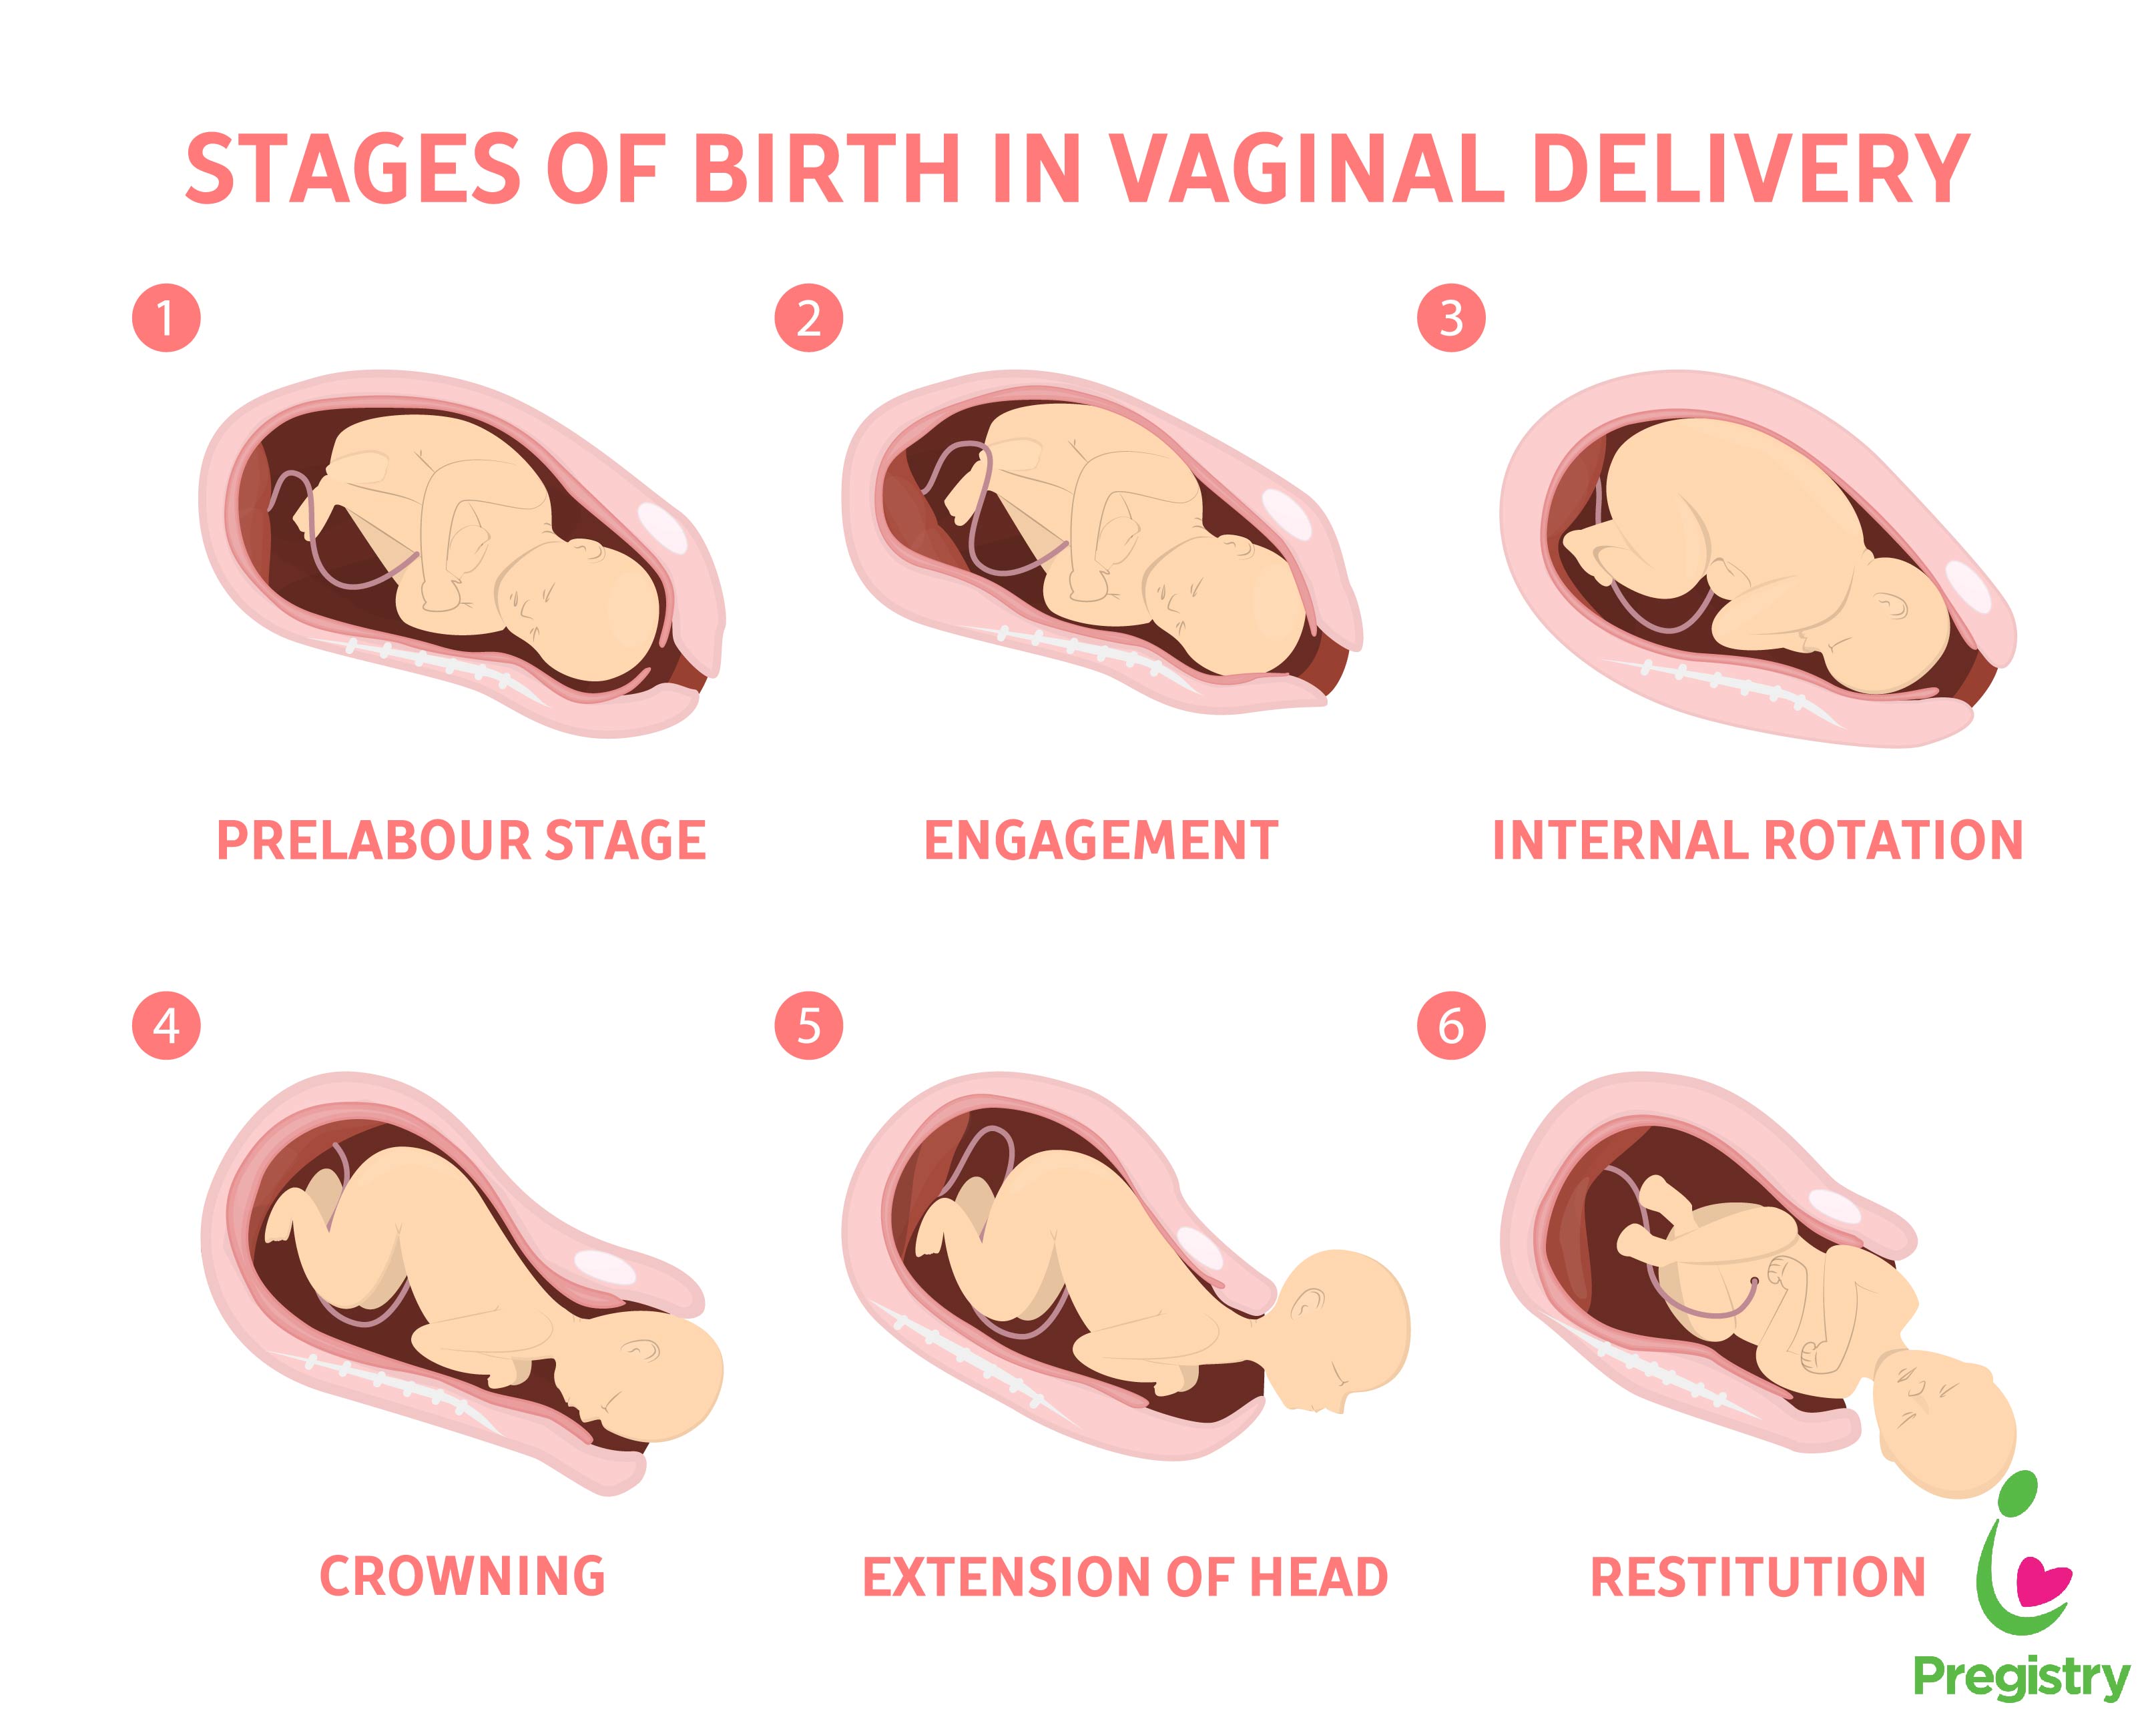

Во время беременности, положение плода имеет большое значение для мамы и малыша. Одним из типичных положений является продольное предлежание головное. В этом положении голова малыша находится внизу, а ножки - наверху. Это положение достаточно распространено и предпочтительно для естественных родов.

Биомеханизм родов в переднеголовном предлежании

Биомеханизм родов таблица

Биомеханизм родов таблица